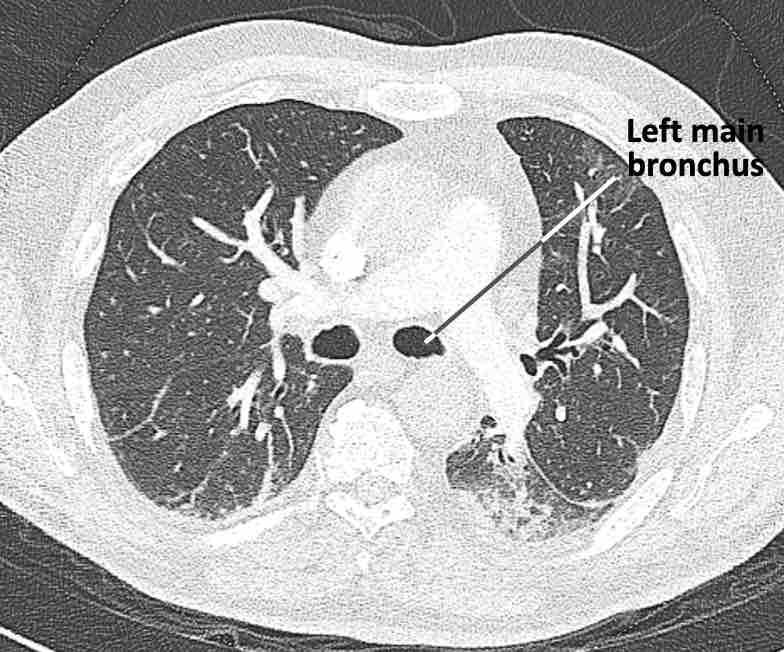

Phế quản trên CT

Cuộn qua các hình ảnh để quan sát khí quản phân chia thành phế quản chính phải và trái, sau đó tiếp tục phân chia thành các phế quản thùy và phế quản phân thùy.